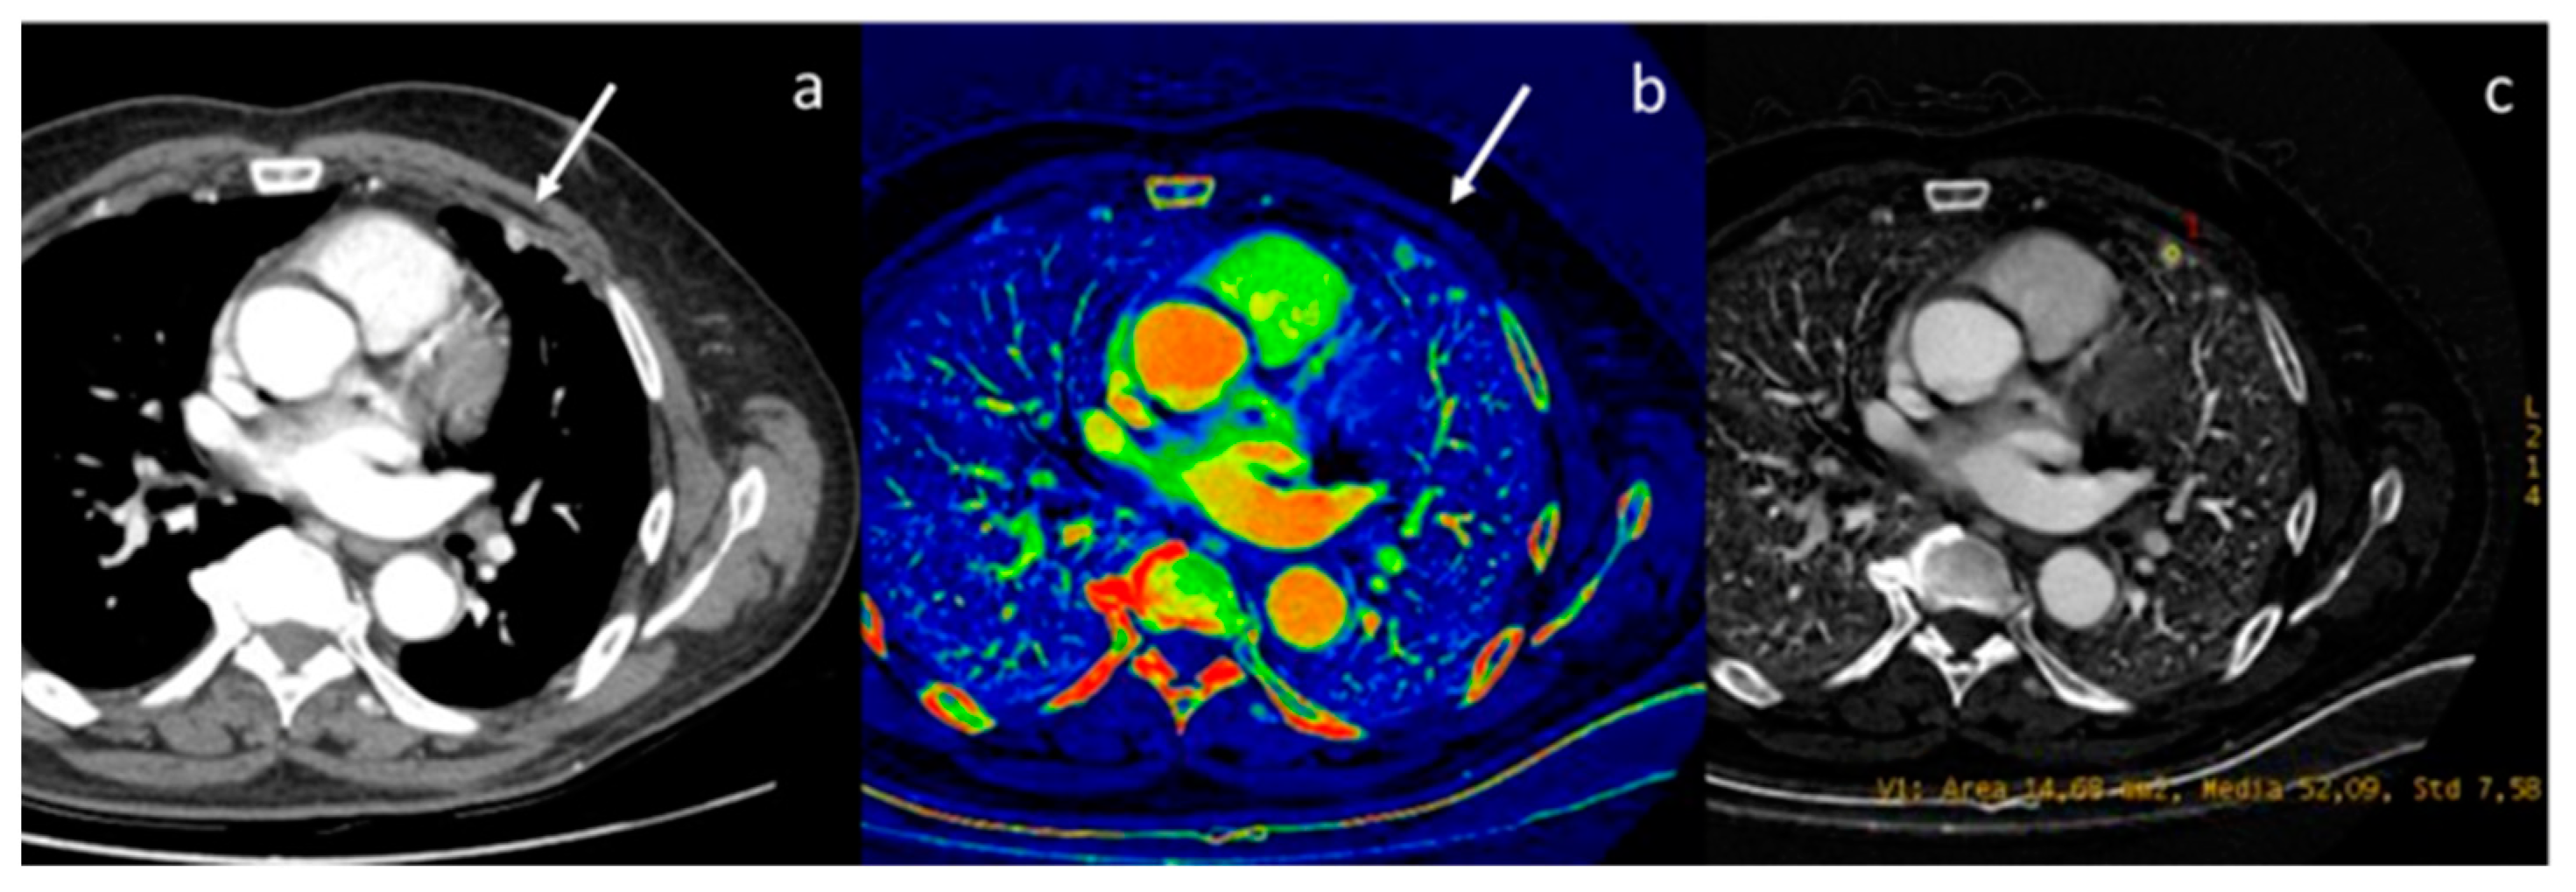

- Li, W.; Liu, M.; Yu, F.; Zhu, W.; Yu, X.; Guo, X.; Yang, Q. Detection of left atrial appendage thrombus by dual-energy computed tomography-derived imaging biomarkers in patients with atrial fibrillation. Front. Cardiovasc. Med. 2022, 9, 809688. [Google Scholar] [CrossRef] [PubMed]